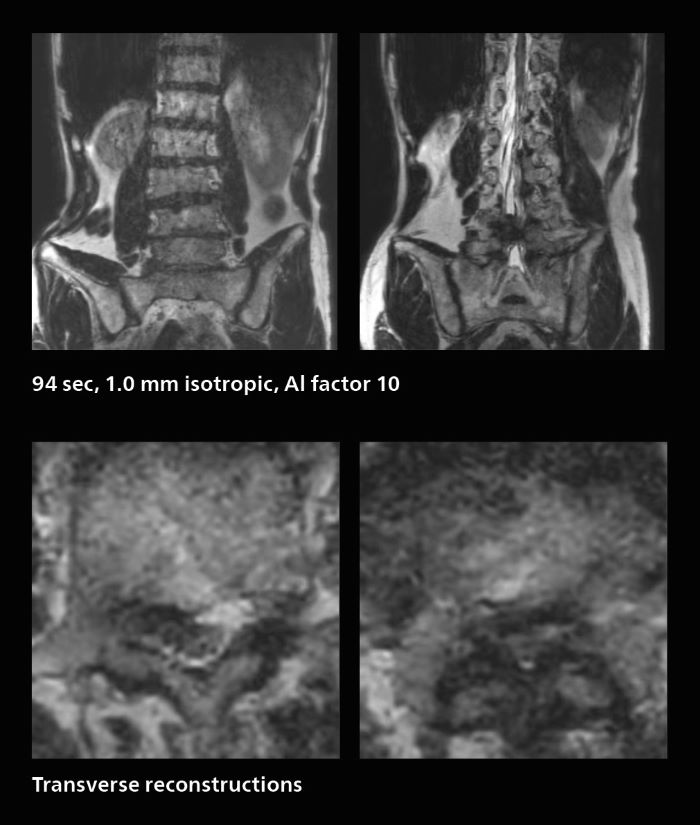

Many patients who must undergo a lumbar spine examination suffer from back pain. For these patients it is difficult to maintain the imaging position long enough to successfully complete the examination. “In such cases, using SmartSpeed allows us to perform volume imaging, so that we acquire only one high resolution 3D sequence in a short time and then reconstruct the other orientations from that,” Dr. Katahira says. “This is highly advantageous because the patient needs only endure a short exam time, whereas before it was necessary to acquire a larger number of sequences in total. We have seen that the shorter time has allowed us to scan patients who previously could not finish the exam. This is a great advantage.”

A patient arrived saying that undergoing MRI was not possible because of severe back pain and leg pain, was imaged with SmartSpeed in only 94 seconds. The scan was diagnostic and afterwards the patient confirmed that it only took a little while. Performed on Elition X.

The hospital’s fast lumbar spine ExamCard includes T2W SpineVIEW, 1:40 min, 1.0 mm isotropic, acceleration factor 12.